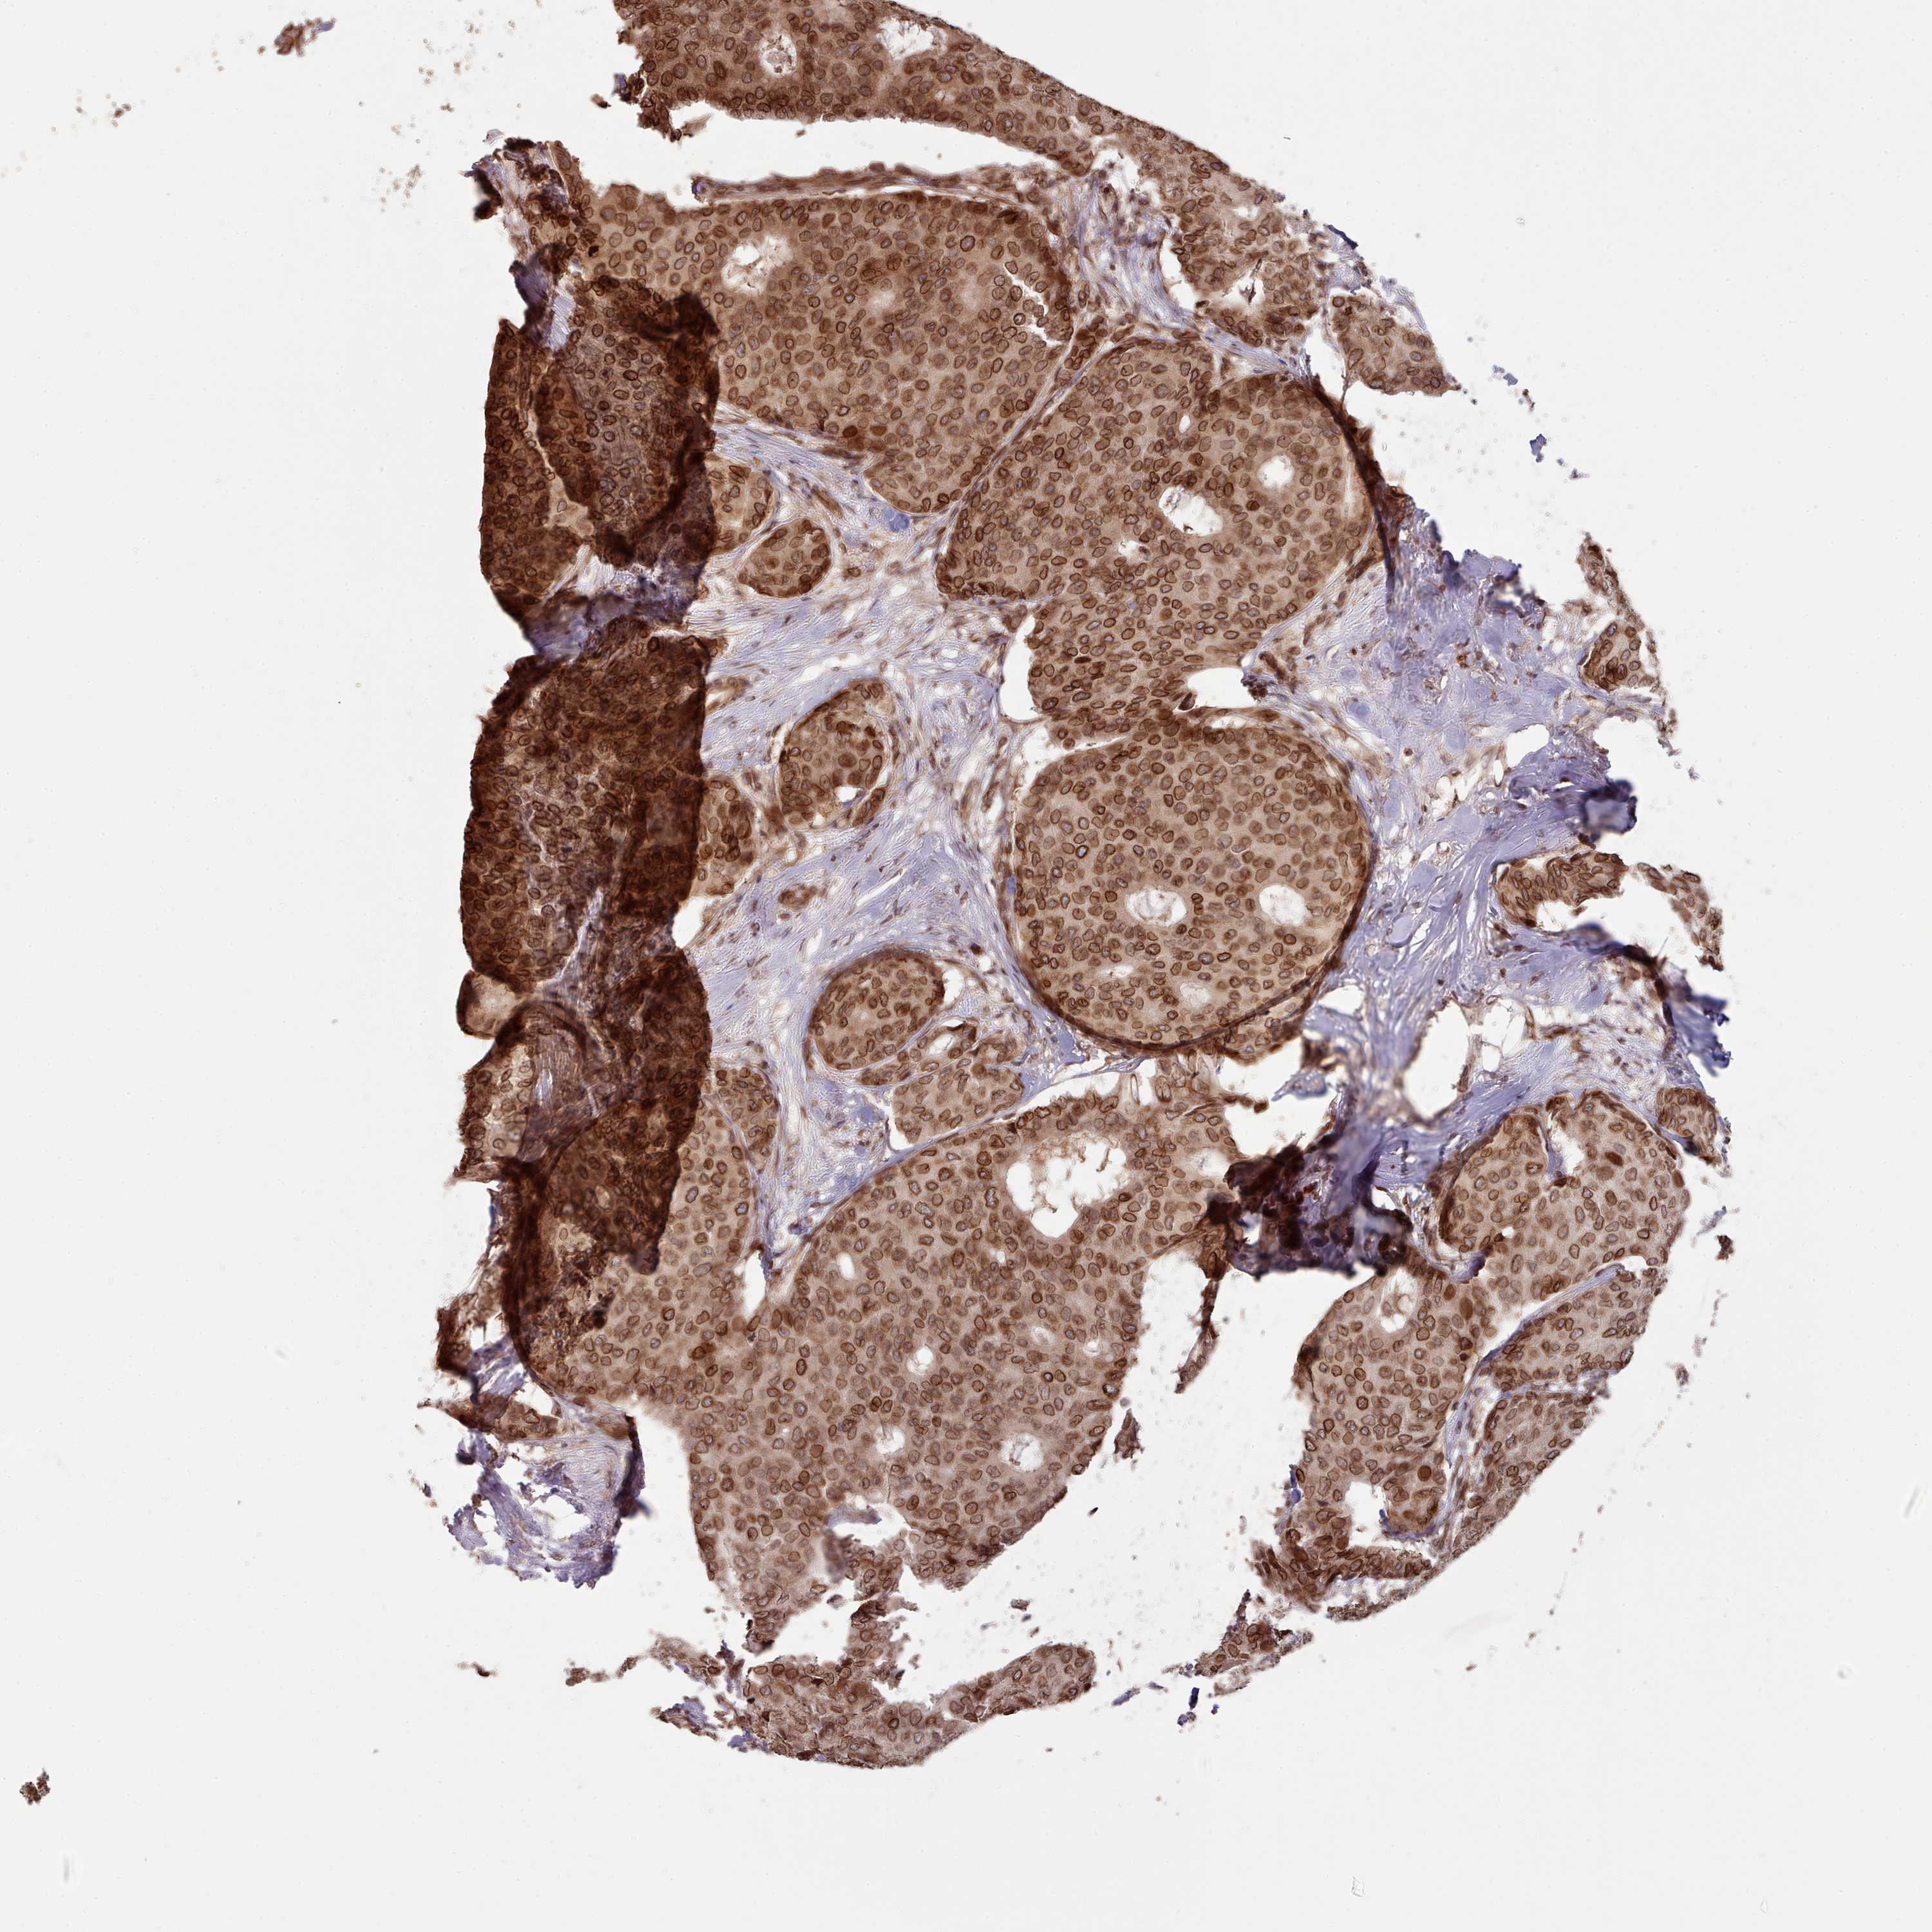

BRCA TCGA BRCA VALIDATION PROTEIN EXPRESSION

ANTIBODIES

AND

VALIDATION